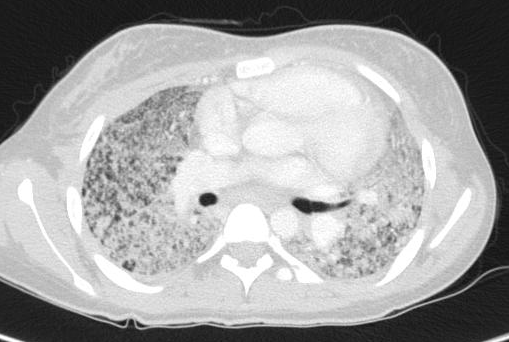

Viene dunque eseguita una radiografia del torace che mostra un quadro di infiltrazione micronodulare bilaterale diffusa (Figura 1) confermato anche alla TAC (Figura 2).

Figura 2. Presenza di numerosissime piccole opacit� di tipi interstiziale e micronodulare, grossolane tumefazioni linfonodali in sede mediastinica.